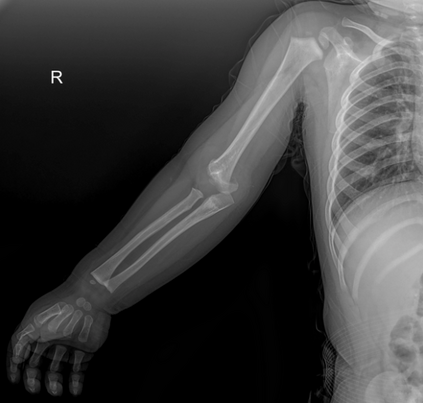

In this study, we aim to initiate the development of Radiology Foundation Model, termed as RadFM.We consider the construction of foundational models from the perspectives of data, model design, and evaluation thoroughly. Our contribution can be concluded as follows: (i), we construct a large-scale Medical Multi-modal Dataset, MedMD, consisting of 16M 2D and 3D medical scans. To the best of our knowledge, this is the first multi-modal dataset containing 3D medical scans. (ii), We propose an architecture that enables visually conditioned generative pre-training, allowing for the integration of text input interleaved with 2D or 3D medical scans to generate response for diverse radiologic tasks. The model was initially pre-trained on MedMD and subsequently domain-specific fine-tuned on RadMD, a radiologic cleaned version of MedMD, containing 3M radiologic visual-language pairs. (iii), we propose a new evaluation benchmark that comprises five tasks, aiming to comprehensively assess the capability of foundation models in handling practical clinical problems. Our experimental results confirm that RadFM significantly outperforms existing multi-modal foundation models. The codes, data, and model checkpoint will all be made publicly available to promote further research and development in the field.